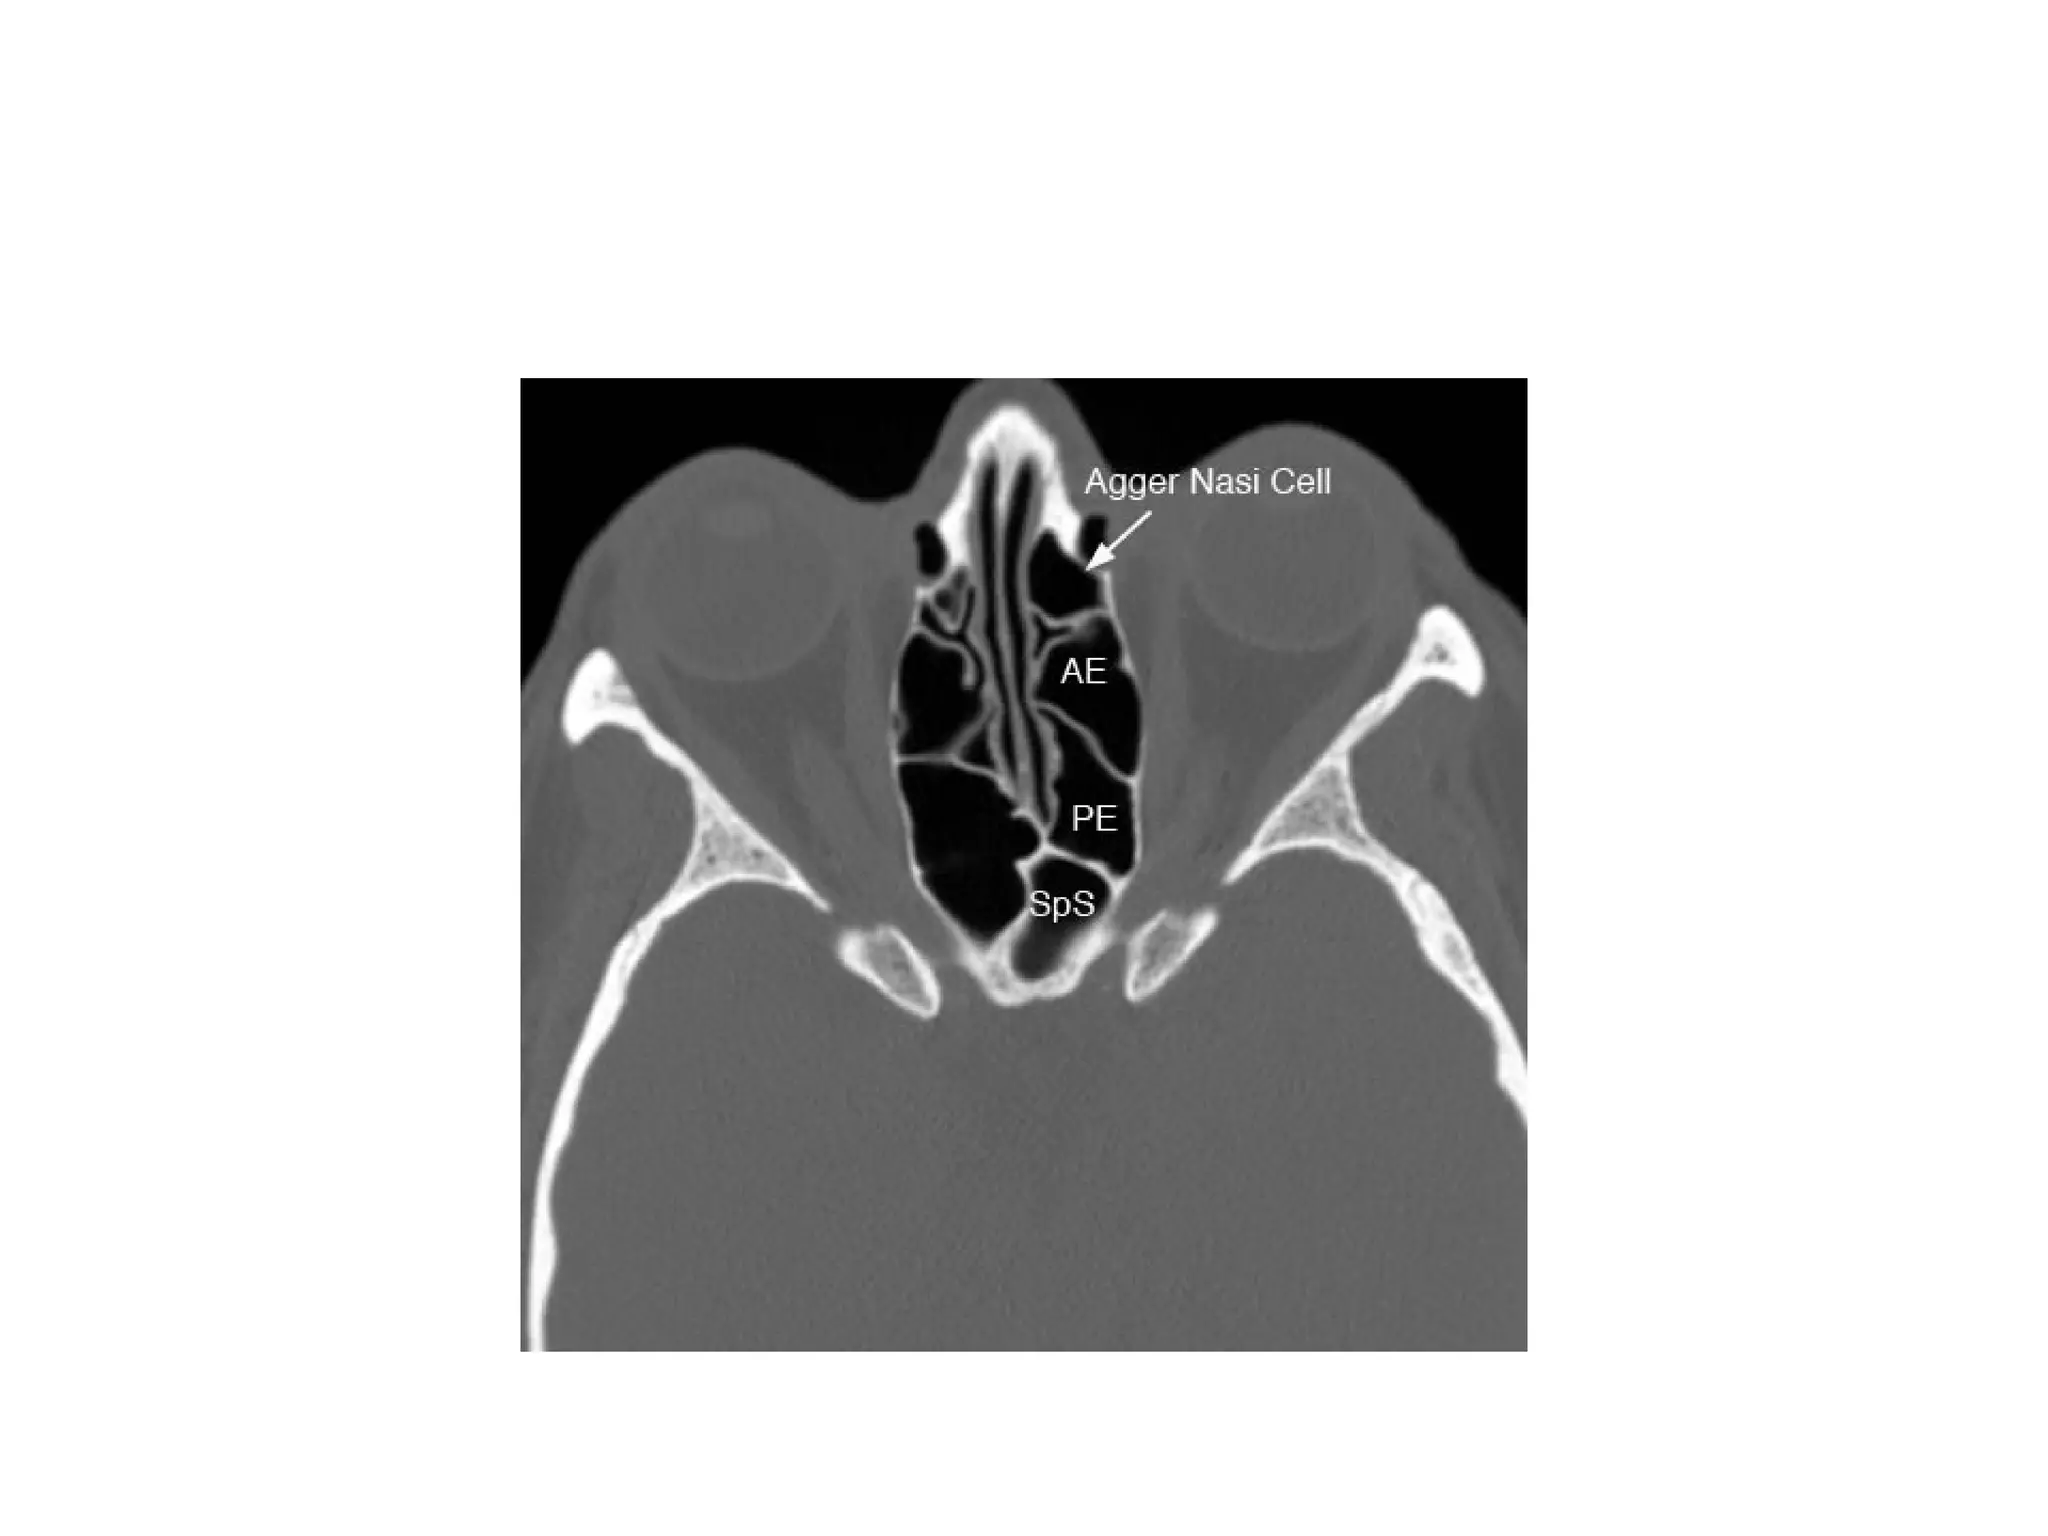

Agger Nasi Cell termAgger in Latin - Mound/Eminence. • anterior to the antero superior attachment of the middle turbinate and borders the frontal recess. • its size may directly influence the patency of the frontal recess. These agger nasi cells are commonly involved in the pathogenesis of the formation of frontal • mucocele. • It is the 1st prominent anatomical landmark encountered in FESS

•sphenoid sinus (SpS) andthe sphenoethmoidal recess marked by the (*). •(AE: anterior ethmoid, PE: posterior ethmoid, CC: carotid canal, NS: nasal septum)